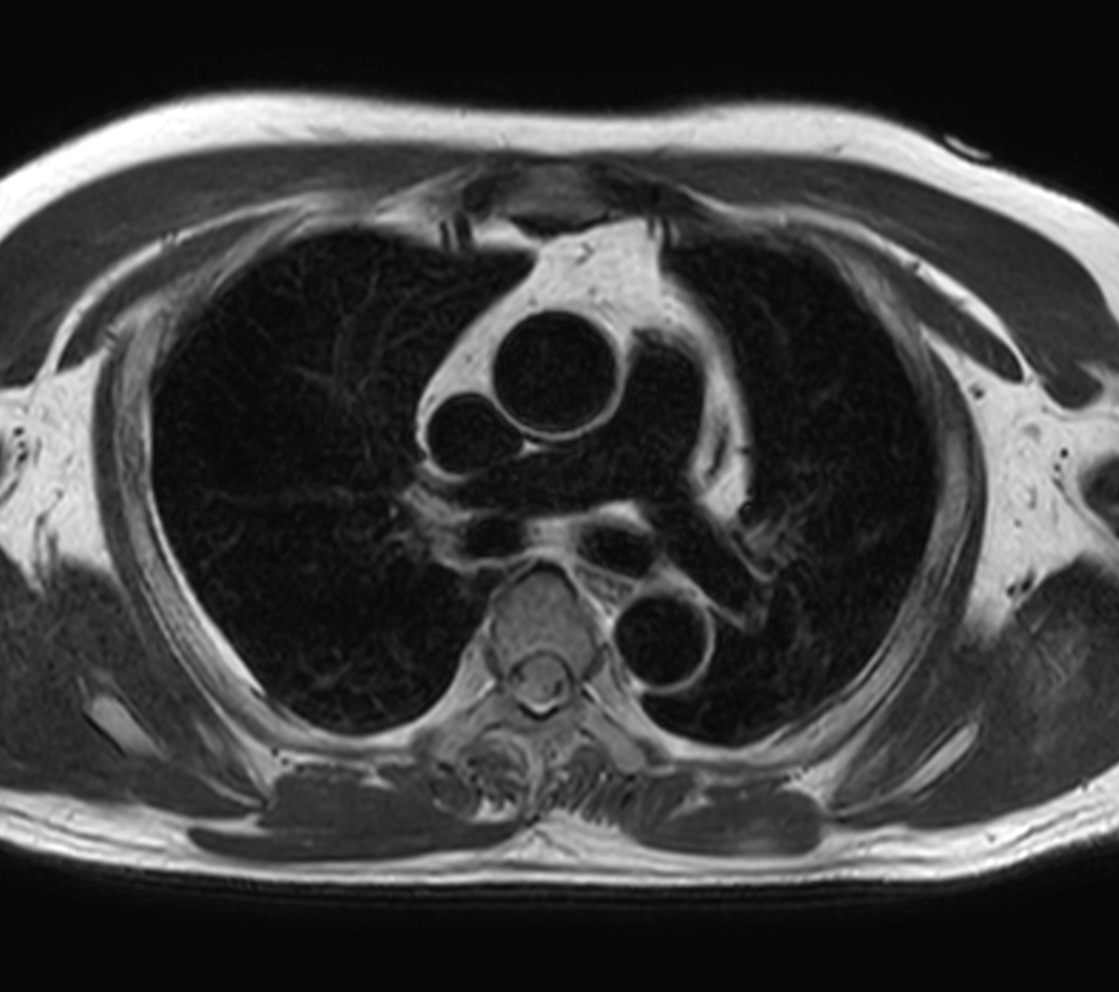

Axial T2w STIR - Black Blood